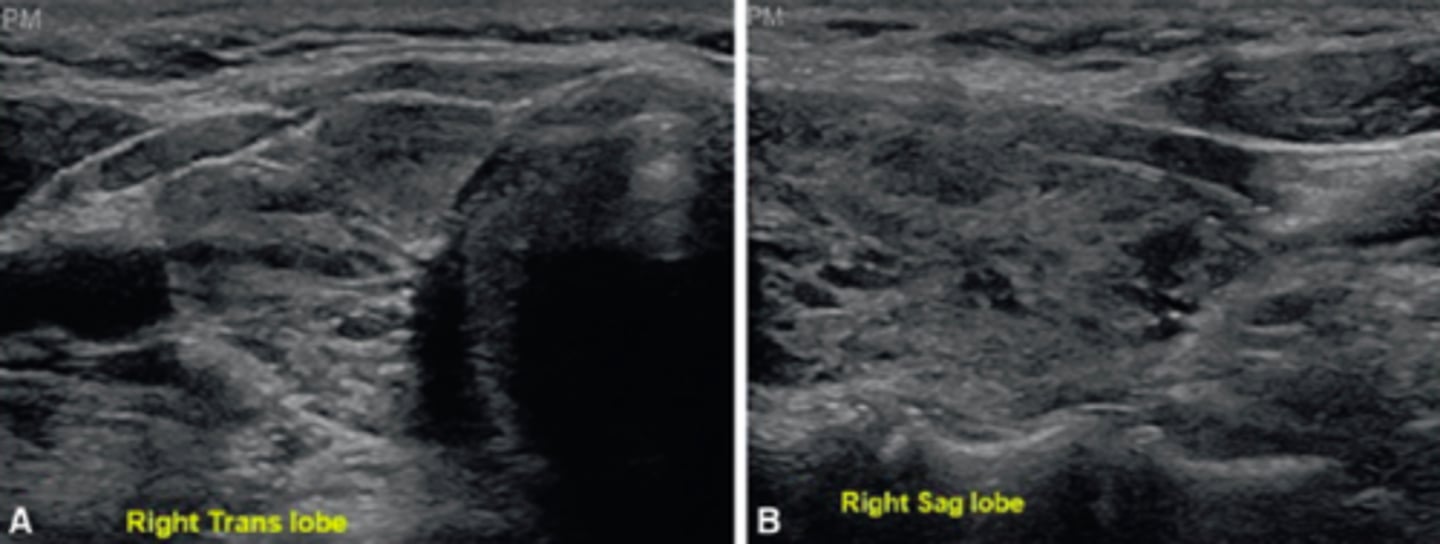

6. The patient in Figure 12-23 complained of weight gain, menorrhagia, and increased cold sensitivity. What is the most likely diagnosis?

a. Parathyroiditis

b. Graves disease

c. Multiple intrathyroid parathyroid glands

d. Autoimmune lymphocytic thyroiditis